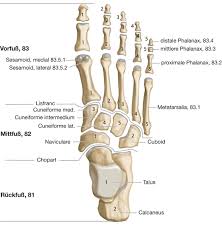

Fußknochen an der seite. Nachdem der erste Anlauf ein Eltern- Lehrerinnen- Team auf die Beine zu stellen im vergangenen Jahr an körperlichen Gebrechen gebrochener Fußknochen gescheitert war starteten wir in diesem Jahr einen neuen Versuch lauffreudige Menschen für den Hanauer Stadtlauf zu begeistern. Der Fuß besteht aus Fußwurzelknochen Mittelfuß und den fünf Zehen auch Vorfuß genannt. Der Fuss ist an der Stelle mit dem Körper verbunden wo Knochen des Rückfusses auf das Schien- und Wadenbein treffen Knöchel.

Den gesamten Komplex bilden außerdem Gelenke Fußwurzelgelenke Gelenke der Mittelfußknochen und Zehengelenke viele für die. Eine weitere Ursache für Schmerzen an der Fußaußenseite ist die Fraktur des fünften Mittelfußknochens. Der menschliche Fuß besteht aus 26 Knochen.

In der Klinik wird der Fuß aus funktionellen Gesichtspunkten in drei Abschnitte unterteilt die sich von der anatomischen Gliederung unterscheiden. Wir zeigen dir hier effektive Übungen mit denen dein Spreizfuß bald der Vergangenheit angehören kann. Trochanter grch der Rollhügel sd am Oberschenkelknochen.